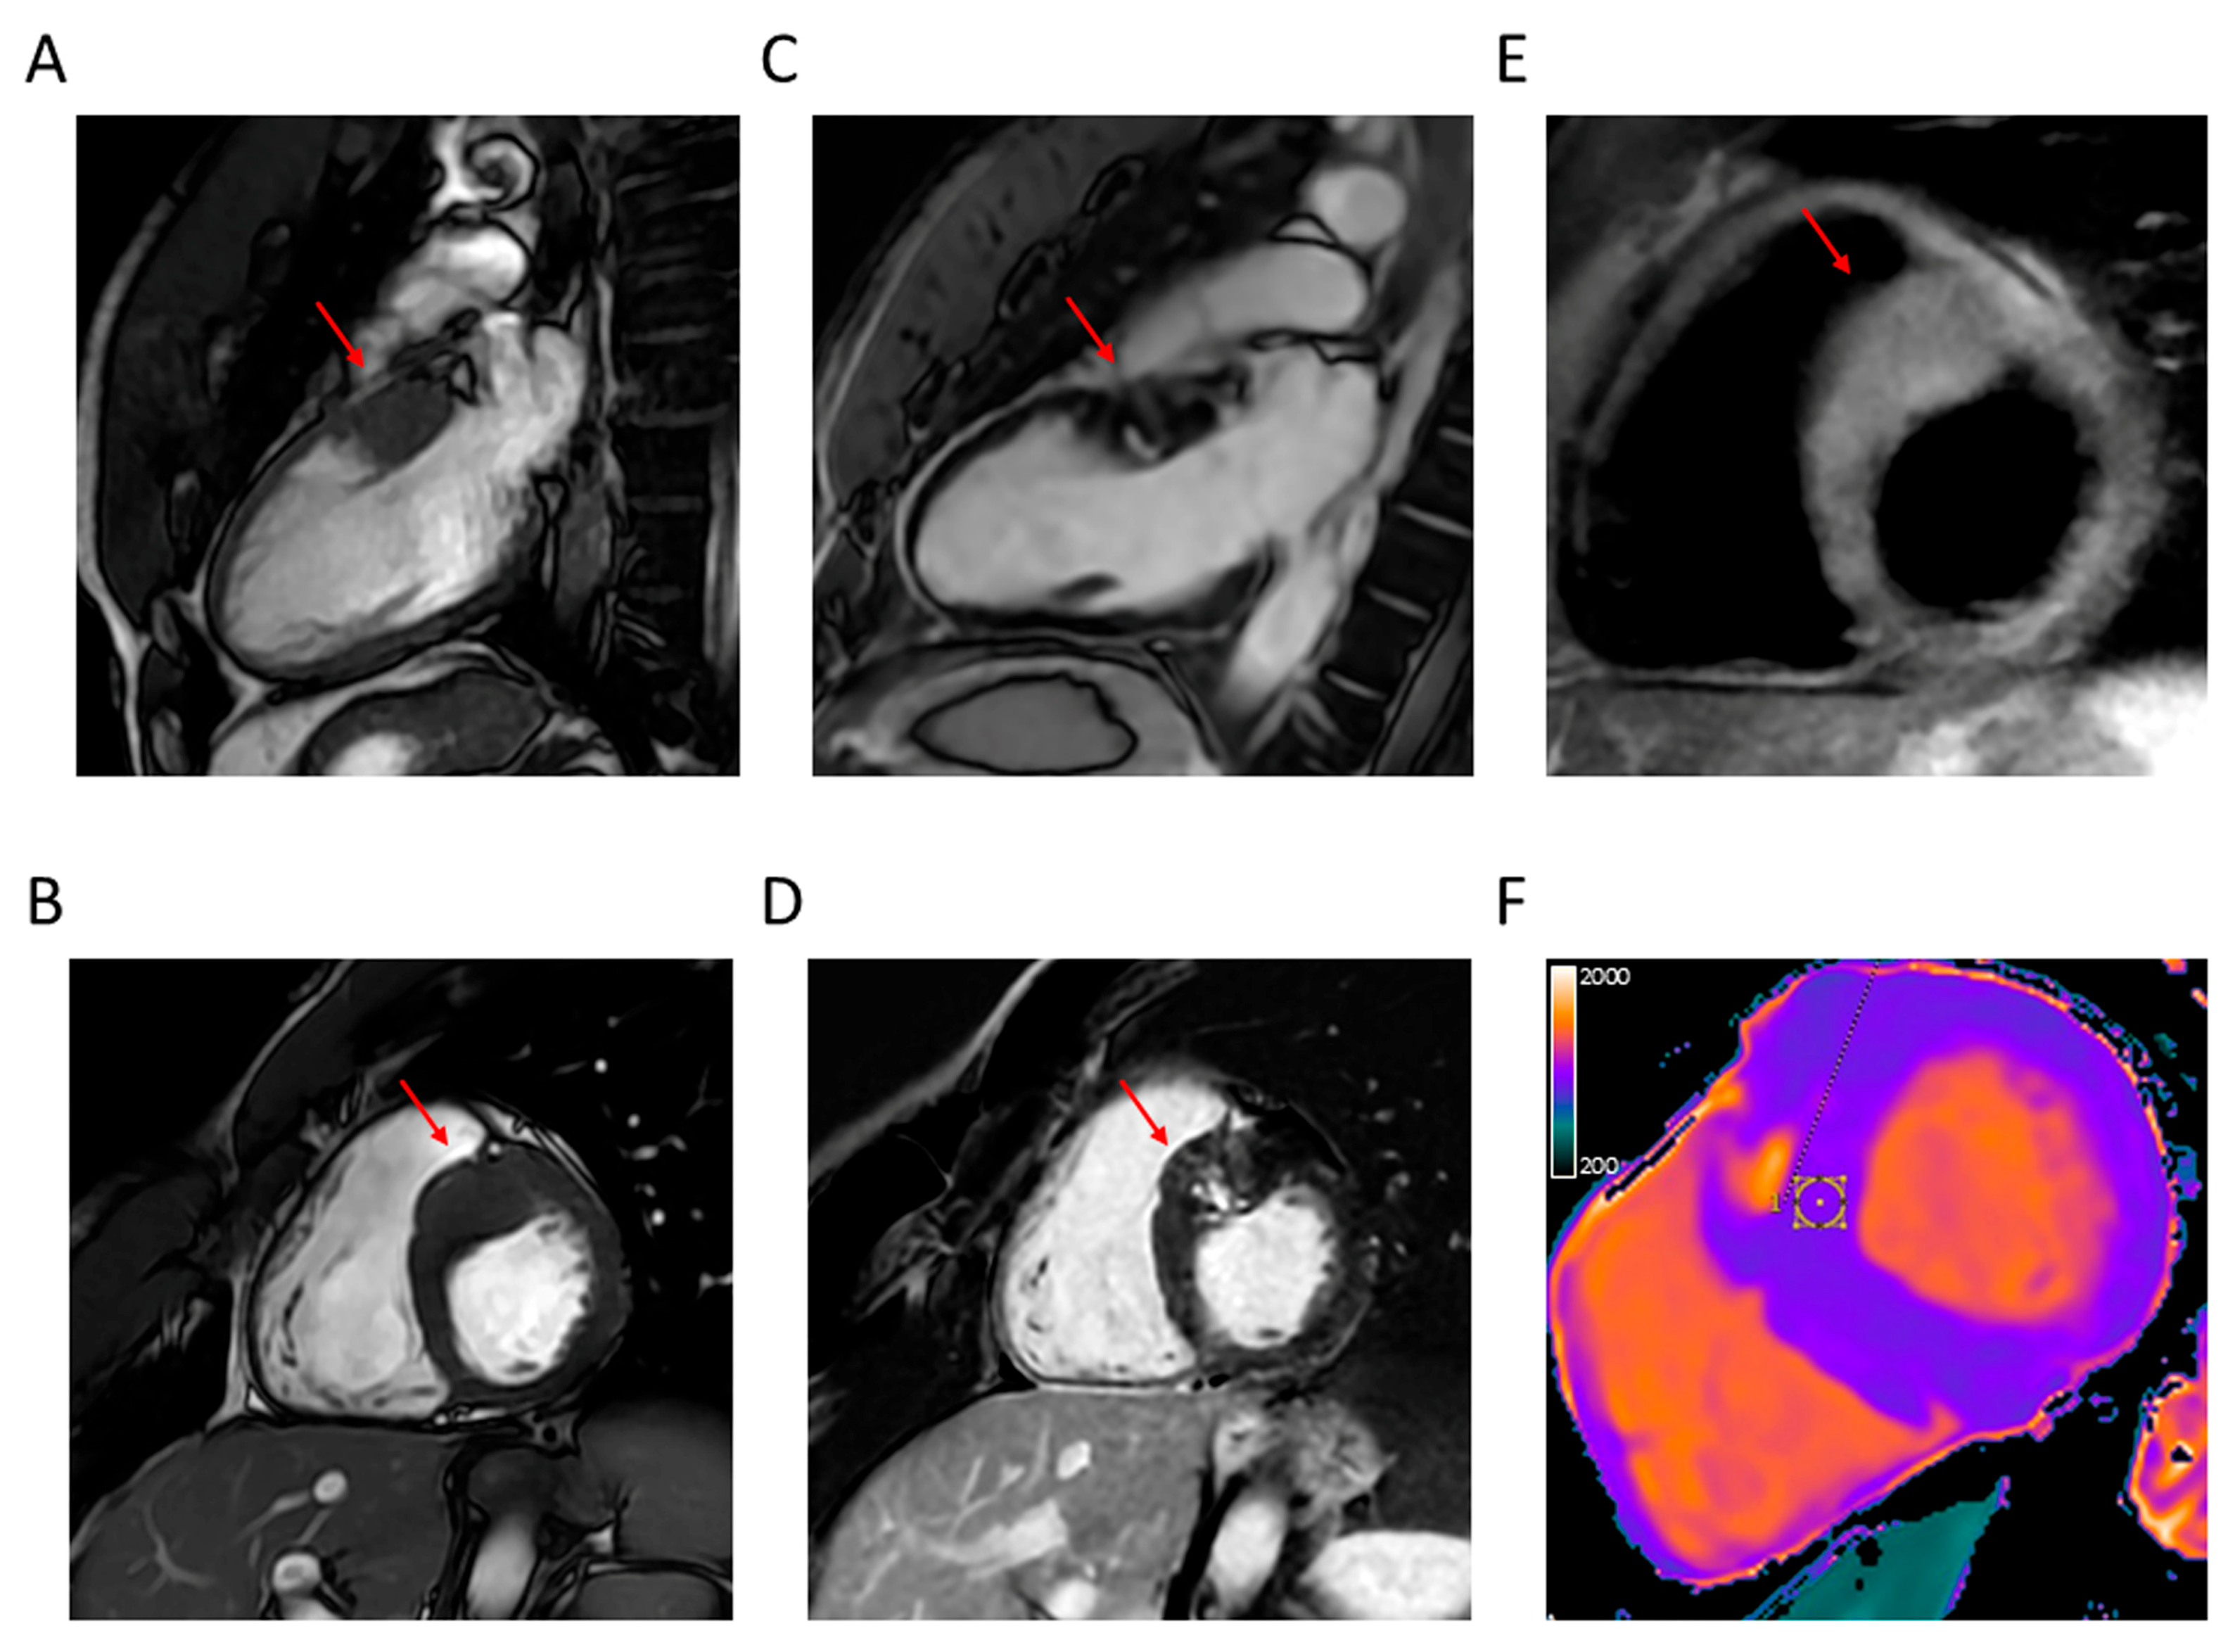

4.2. Apical Aneurysm

4.3. LVOTO

4.4. LV Function